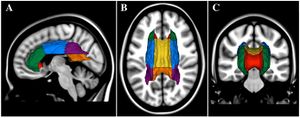

Thalamic Shape and Volume Abnormalities in Female Patients with Panic Disorder

Publication: PLoS One. 2018 Dec 19;13(12):e0208152. PMID: 30566534 | PDF Authors: Asami T, Yoshida H, Takaishi M, Nakamura R, Yoshimi A, Whitford TJ, Hirayasu Y. Institution: Department of Psychiatry, Graduate School of Medicine, Yokohama City University, Yokohama, Japan. Abstract: The thalamus is believed to play crucial role in processing viscero-sensory information, and regulating the activity of amygdala in patients with panic disorder (PD). Previous functional neuroimaging studies have detected abnormal activation in the thalamus in patients with PD compared with healthy control subjects (HC). Very few studies, however, have investigated for volumetric abnormalities in the thalamus in patients with PD. Furthermore, to the best of our knowledge, no previous study has investigated for shape abnormalities in the thalamus in patients with PD. Twenty-five patients with PD and 25 HC participants (all female) were recruited for the study. A voxel-wise volume comparison analysis and a vertex-wise shape analysis were conducted to evaluate structural abnormalities in the PD patients compared to HC. The patients with PD demonstrated significant gray matter volume reductions in the thalamus bilaterally, relative to the HC. The shape analysis detected significant inward deformation in some thalamic regions in the PD patients, including the anterior nucleus, mediodorsal nucleus, and pulvinar nucleus. PD patients showed shape deformations in key thalamic regions that are believed to play a role in regulating emotional and cognitive functions. Funding:

Female patients with panic disorder showed significant inward deformation of shape in the bilateral thalamus compared with female healthy control subjects (false discovery rate corrected, P < .05). These regions included (in the right thalamus) the anterior nucleus, medial mediodorsal nucleus, and lateral posterior nuclei (orange), and the medial part of pulvinar nucleus (green). In the left thalamus, the anterior nucleus, ventro-lateral nucleus, ventral anterior nucleus (orange), the medial part of pulvinar nucleus (green), and the lateral part of pulvinar nucleus (yellow) were affected. Abbreviations: Rt, right; Lt, left; ant, anterior view; post, posterior view; lat, lateral view; med, medial view; sup, superior view; inf, inferior view; 3D images were created using 3D Slicer. |